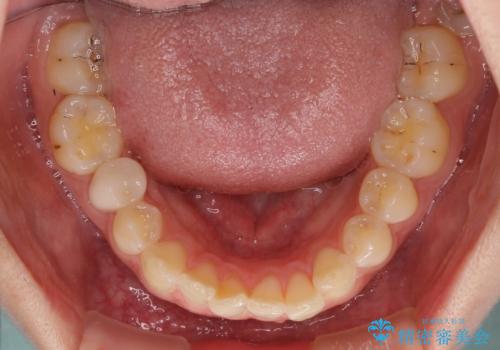

奥歯の咬み合わせの改善は、インビザライン単独では達成しきれないことがあるため、ワイヤー矯正などの補助装置を併用する場合があります。

インビザライン単独の場合と比べ、治療結果は大きく異なります。